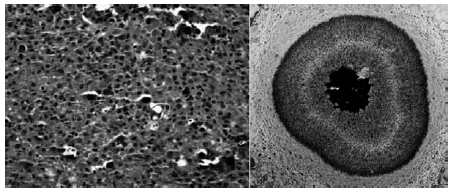

A classificação histopatológica do seguinte quadro, em relação aos parâmetros mínimos microscópicos, aplica-se à qual doença?

Incluir:

% Total de glomérulos

% Proliferação endocapilar

% Crescentes celulares ou fibrocelulares

% Necrose

% Esclerose glomerular global